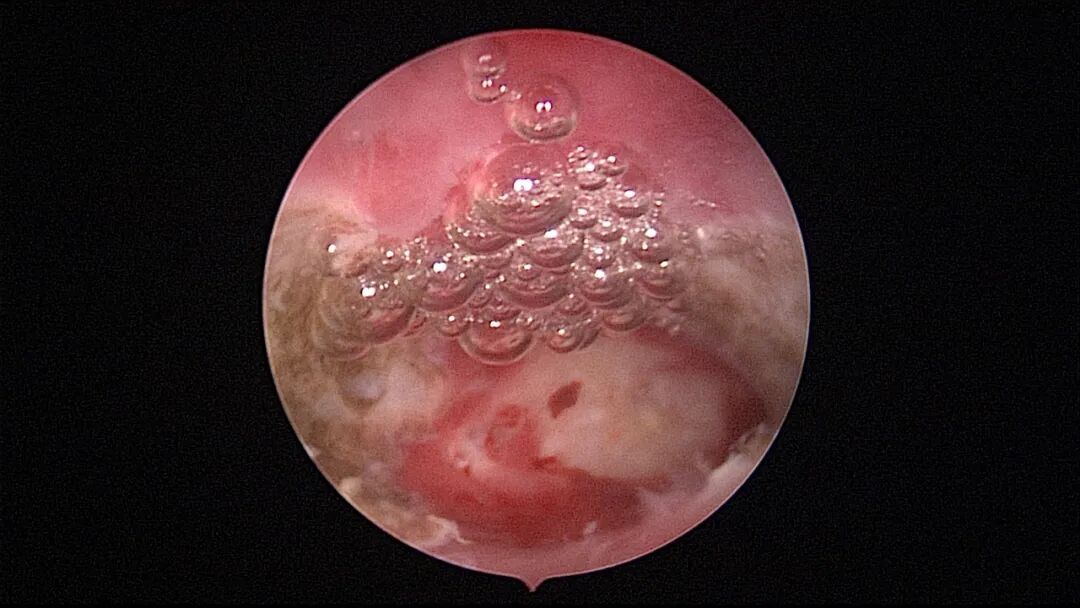

病例3:30岁,G8P1,顺产1次。月经淋漓不净10余天,月经周期第11天B超示宫腔回声宽约0.5cm,内可见絮状回声,有流动感。宫腔镜探查,宫颈管见血迹,宫腔粘连,内膜草莓状,单极电针分粘,内膜活检,病检为增殖期样子宫内膜伴出血。

| ||||